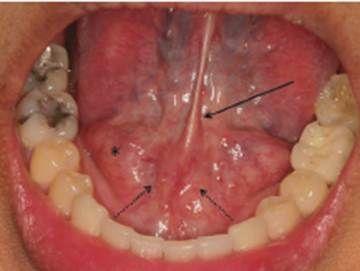

3.頜下間隙感染:智齒冠周炎或者下頜磨牙根尖周炎久治不愈,細(xì)菌通過頜下淋巴結(jié)擴(kuò)散到頜下三角,出現(xiàn)下頜部腫脹疼痛,舌下腫脹,也可出現(xiàn)張口困難,需要緊急進(jìn)行手術(shù)排膿引流。2.咀嚼肌下間隙感染:當(dāng)?shù)谌パ拦谥苎滓卜Q為智齒感染時(shí),如果沒有時(shí)間進(jìn)行治療的話,細(xì)菌容易擴(kuò)散到咀嚼肌下間隙,引起感染,可出現(xiàn)半個(gè)臉腫脹疼痛,也可出現(xiàn)張口困難,需要緊急手術(shù)排膿抗菌消炎處理,不然的話,有可能引起下頜骨骨髓炎。

趙先生被緊急推進(jìn)了手術(shù)室,術(shù)前麻醉,消毒等準(zhǔn)備工作完成以后,醫(yī)生順著腫脹的下頜依次切開皮膚、皮下組織和筋膜,到達(dá)頜骨下間隙,引流膿液,緊接著又切開下頜舌骨肌,進(jìn)一步引流舌下間隙膿液,隨后用血管鉗深入膿腔,進(jìn)行擴(kuò)張引流,用吸引器吸進(jìn)膿液后,放置引流條進(jìn)行引流,趙先生被推進(jìn)病房后進(jìn)行輸液,避免發(fā)生術(shù)后感染,我們衷心希望趙先生能夠早日康復(fù)。